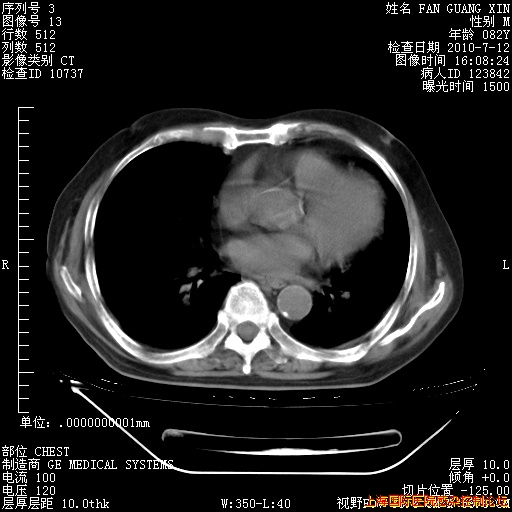

今天复查CT

今天CT

整整相隔30天的肺部CT好像有所好转啊。甲强龙减量第3天,需要观察体温。

海管,自昨日你和我通完话后,不知您岳父消化道症状有无缓解?体温怎样?阅读7.12日胸部ct,个人认为目前激素治疗是有效的,甲强龙减量是适宜的。因在抗痨治疗,需密切观察肝功、肾功能和血常规。不过,老年、长期住院和大量使用激素,很担心菌群失调发生